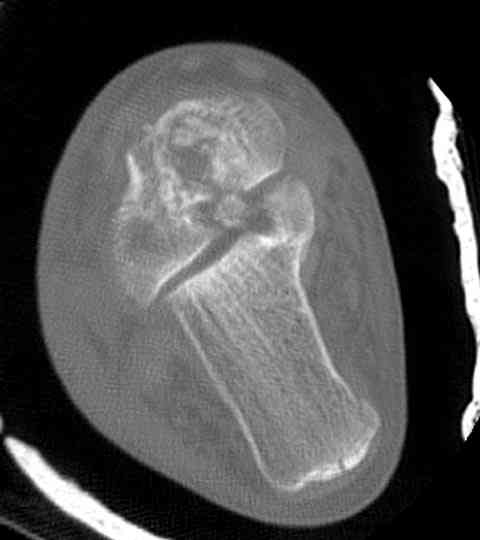

Случай с множественным оскольчатым переломом тарана оперированный из двойного доступа.

Через 8 мес.: